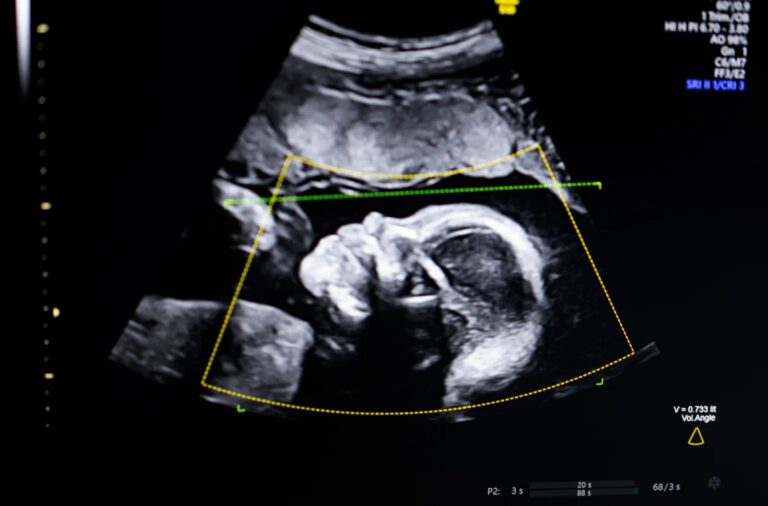

Une startup issue de la scène technologique américaine vient de franchir un seuil décisif dans l’utilisation de l’intelligence artificielle en médecine. BioticsAI, lauréate du TechCrunch Disrupt Battlefield 2023, a annoncé avoir obtenu l’autorisation de la Food and Drug Administration (FDA) pour son logiciel d’analyse par IA destiné à détecter les anomalies fœtales à partir d’images d’échographie. Une avancée qui pourrait transformer en profondeur la surveillance des grossesses, notamment dans les zones où la qualité des soins prénataux reste inégale.

Après avoir appris à coder et étudié l’informatique à l’Université de Californie à Irvine, Bustami s’est associé en 2021 à Salman Khan, Chaskin Saroff et au Dr Hisham Elgammal pour fonder BioticsAI. Leur objectif était clair : mettre la vision par ordinateur au service de la fiabilité des échographies prénatales. Le logiciel développé par l’équipe utilise l’IA pour évaluer la qualité des images, vérifier la complétude anatomique, automatiser les rapports médicaux et s’intégrer directement dans les flux de travail cliniques existants.

Selon Bustami, le défi n’a pas été tant de créer les modèles d’intelligence artificielle, entraînés sur des centaines de milliers d’échographies issues de populations diverses, que de garantir leur performance dans des conditions réelles. L’enjeu était crucial, notamment pour les groupes les plus exposés aux risques, comme les femmes noires, qui enregistrent aux États-Unis un taux de mortalité maternelle bien plus élevé que la moyenne des pays à revenu élevé. Dans un contexte où les disparités de santé sont largement documentées, la fiabilité de l’outil sur tous les profils de patientes était une condition non négociable.